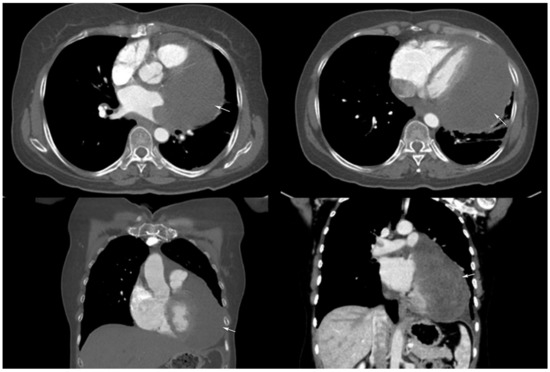

Primary Pericardial Synovial Sarcoma: A Case Report and Literature Review

We report a case of a 52-year-old woman who was referred to our institution with a superior vena cava syndrome and was investigated through echocardiography, CT and MRI revealing a well-defined, encapsulated pericardial mass. The pathology, correlated with the immunohistochemical analysis, concluded it [...] Read more.

We report a case of a 52-year-old woman who was referred to our institution with a superior vena cava syndrome and was investigated through echocardiography, CT and MRI revealing a well-defined, encapsulated pericardial mass. The pathology, correlated with the immunohistochemical analysis, concluded it was an extremely rare primary pericardial synovial sarcoma. The patient underwent surgery and chemotherapy with a 16-month disease-free survival and passed away after a contralateral aggressive relapse. Moreover, we discuss the role of each imaging modality together with their pericardial synovial sarcoma reported features. Full article